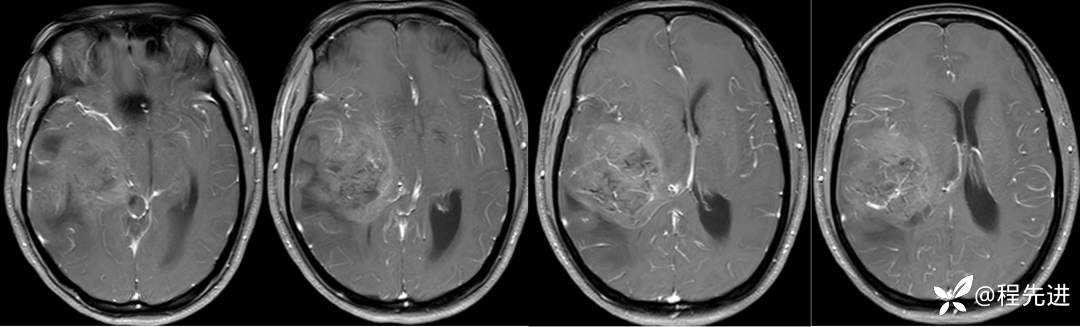

T1+C: